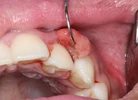

Diş Eti Kanaması

Periimplantitis